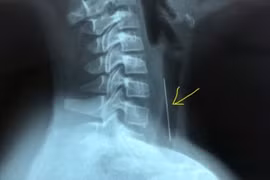

Người bệnh bị bướu cổ hơn 30 năm với kích thước khối u tuyến giáp lớn, chèn ép, đẩy khí quản cổ sang một bên gây khó thở đã được các bác sỹ Bệnh viện Nhân dân Gia Định phẫu thuật thành công.

Bị u tuyến giáp lành tính to không mổ, đến khi nuốt vướng mới đến lại bệnh viện thì u vỡ, chèn ép khí quản, thần kinh thanh quản và thực quản gây nguy hiểm tới tính mạng.

Các bác sĩ Bệnh viện TWQĐ 108 vừa phẫu thuật thành công khối u tuyến giáp khổng lồ với kích thước thùy phải 10x6cm, kích thước thùy trái 12x7cm, phát triển cả lên phía trên và đẩy xuống nền cổ, gây đè hẹp khí quản.